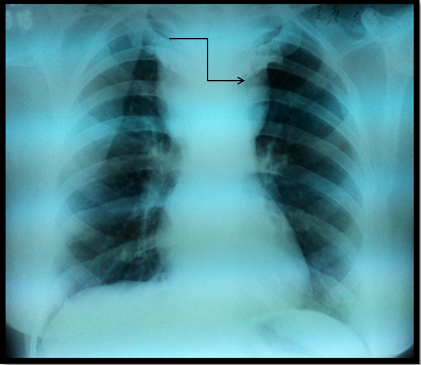

Imaging in form of radiographs of the neck and chest revealed a soft tissue density lesion in the superior mediastinum with well-defined lateral margins; however the inferior margin was not well defined. The trachea was central with no evidence of any compression (Figure 2A & 2B).

Figure 2B Soft tissue swelling in superior mediastinum with well-defined lateral margins (arrow). Inferior margin is ill defined.